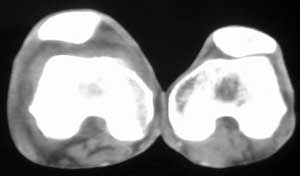

男56涨疼5-6月

右股骨下端包绕股骨见巨大软组织肿块,密度部俊,周围见瘤骨,下端骨皮质侵蚀变薄,骨质周围无骨膜反应, 考虑右股骨软骨肉瘤。

右股骨下段周围软组织肿块伴钙化,相邻股骨骨皮质受累,考虑软组织来源恶性病变

右股骨下段骨肉瘤,软组织内瘤骨,软组织肿块。